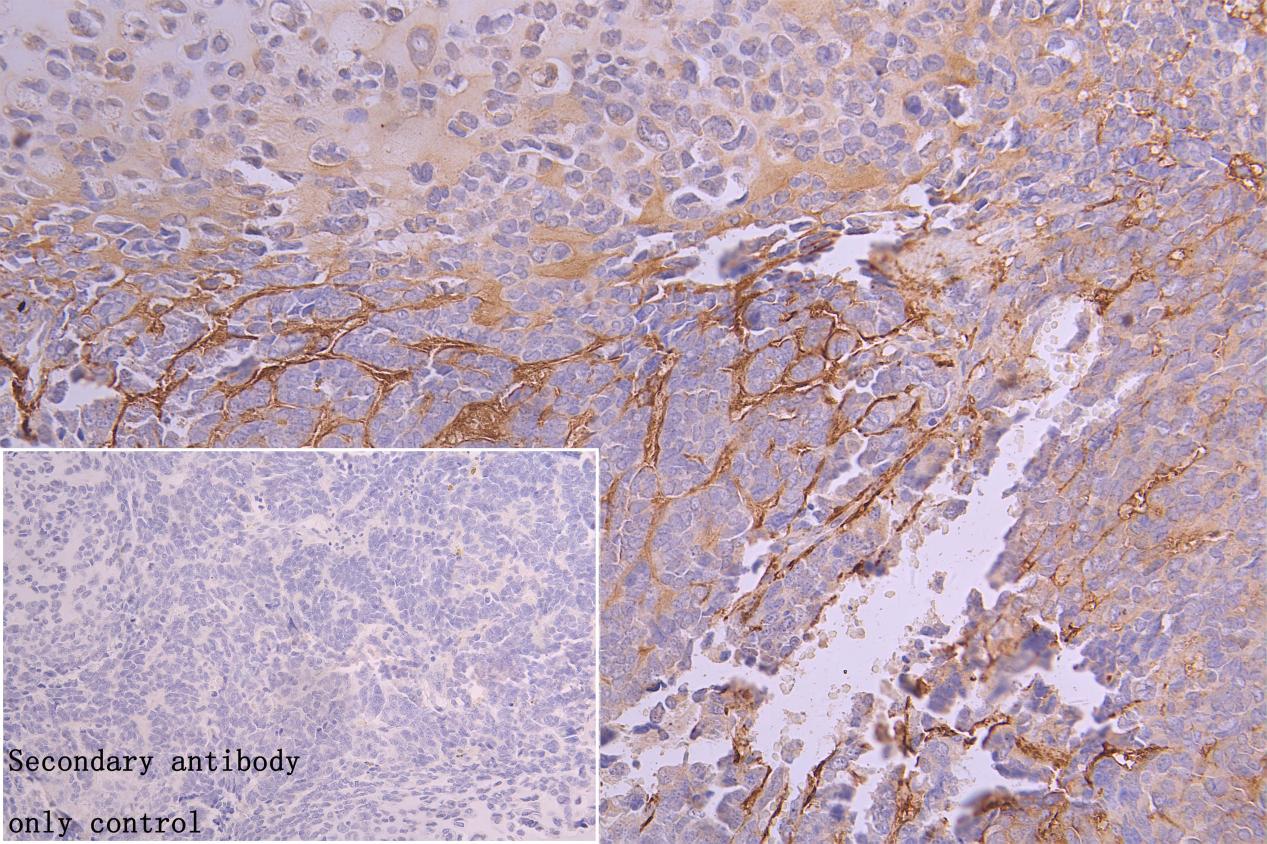

• IHC image of CSB-PA007756LA01HU diluted at 1:100 and staining in paraffin-embedded human ovarian cancer performed on a Leica BondTM system. After dewaxing and hydration, antigen retrieval was mediated by high pressure in a citrate buffer (pH 6.0). Section was blocked with 10% normal goat serum 30min at RT. Then primary antibody (1% BSA) was incubated at 4°C overnight. The primary is detected by a Goat anti-rabbit polymer IgG labeled by HRP and visualized using 0.05% DAB. Secondary antibody only control: uses 1% BSA instead of primary antibody